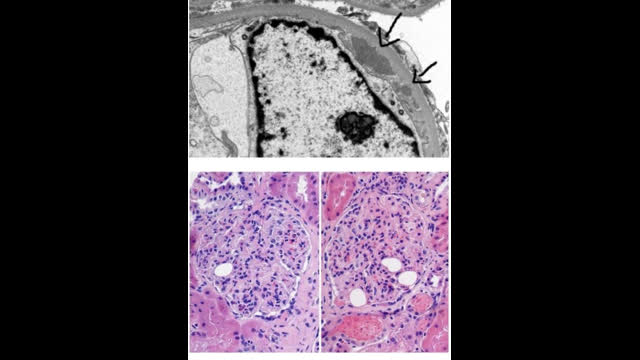

RENAL BIOPSY

-Diffuse proliferative GN changes

-EM - extensive sub endothelial deposits.

-IF positive for C3 ,C1q, IgG